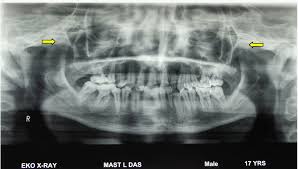

Full Text A Novel Presentation Of Hecht Beals Trismus Pseudocamptodactyly Syndrome Review Of Literature And Holistic Management International Journal Of Case Reports And Images Ijcri